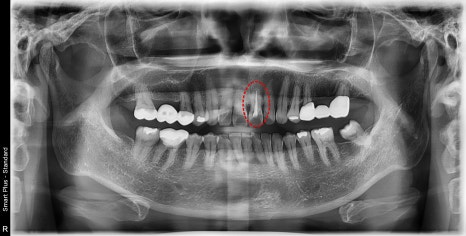

오래전에 대문니에 신경치료를 받으신 환자분이십니다.

치아 주변 플라그도 쌓여있어 잇몸치료도 필요해 보이십니다.

치료 후 시간이 지남에 따라 내부 재료의 변색과

신경치료를 위해 입구를 만든 부분에

충전해 놓은 재료의 오염에 의해 치아가 검게 보입니다.

엑스레이 상에서 뿌리 쪽 염증은 확인되지 않아

내부 오염된 부위를 깨끗이 제거한 후 새로운 충전재를 충천하고

보철 제작을 하기로 했습니다.